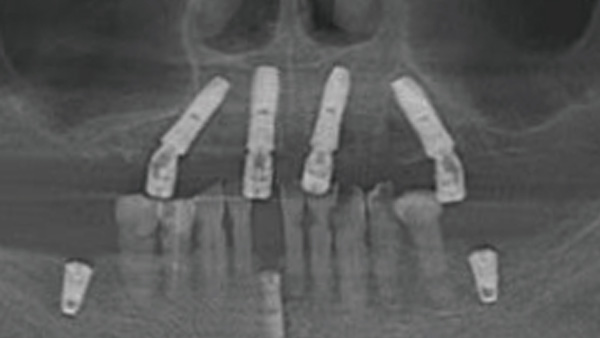

覆蓋所有牙位、即刻種植、即拔即種、全口無牙頜種植